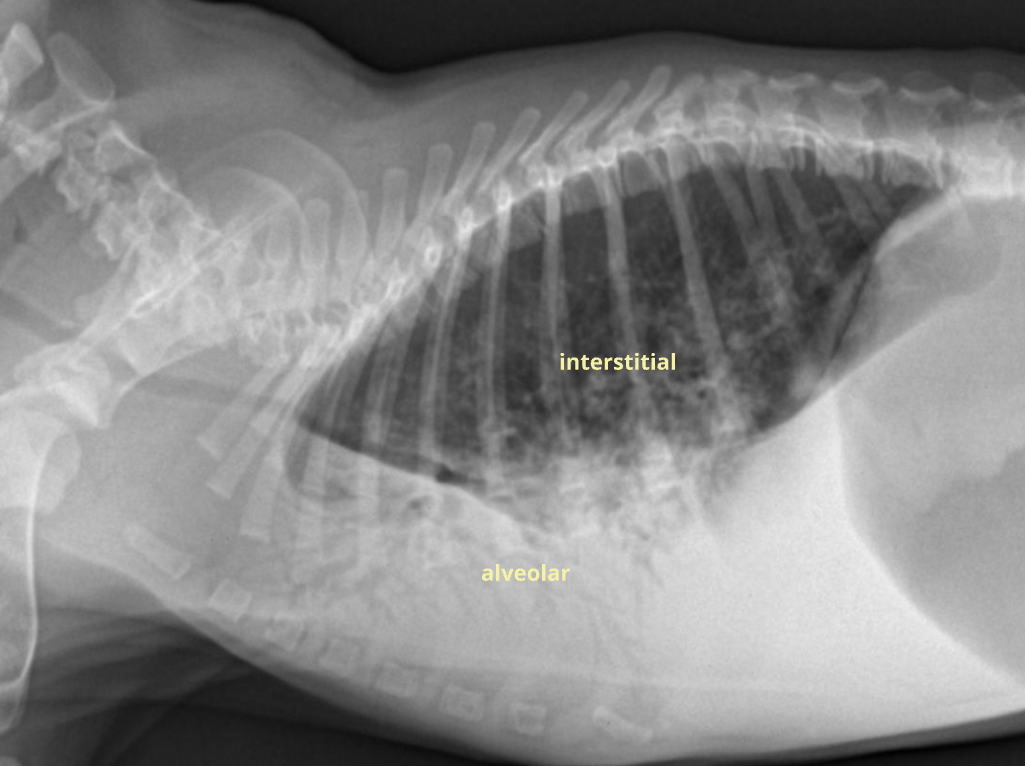

✳️ ==Alveolar pattern==

Fluid, blood, cell 등이 균질하게 차 있음

* interstitial pattern에 비해 진하고 균질함.

- Consolidation (폐경화; 공기 외 다른 게 참)

- Lobar sign (엽과 엽 사이 경계가 드러남)

- Air bronchogram; “Trees in the fog” (폐엽이 차서 기관지가 드러남)

- Cardiac effacement

✳️ Interstitial pattern

벽이 두꺼워지고 공기가 차면서 지저분하게 나타나는 모양.

+ Nodular (구조성 간질 패턴) : 폐결절